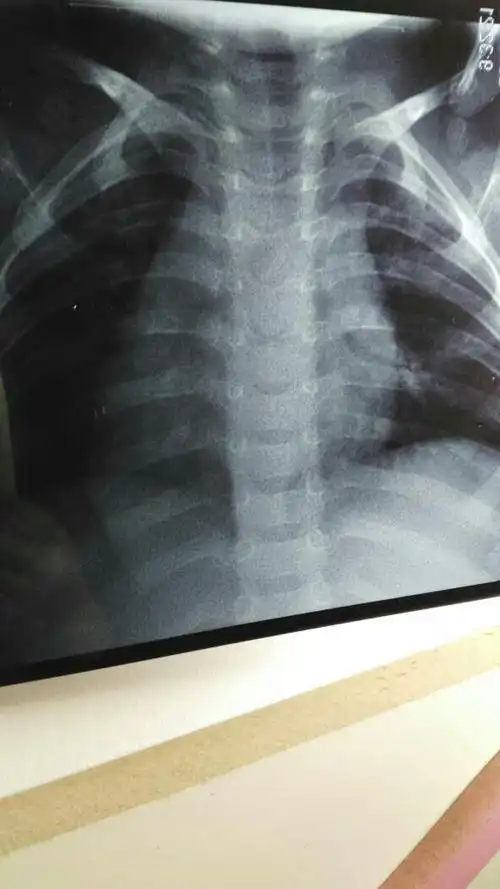

双胞胎反复肺炎的原因,及下一步处理. [病例帖]

男,3岁,因"发热,咳嗽4天"为主诉入院,入院后完善胸部ct提示大叶性肺炎